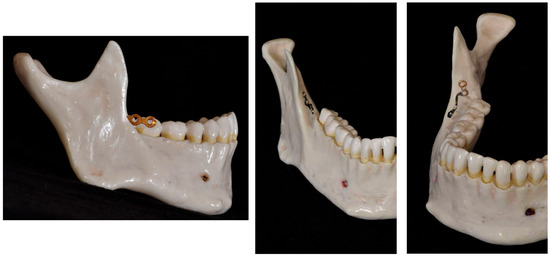

- Yu, J.; Park, J.H.; Bayome, M.; Kim, S.; Kook, Y.-A.; Kim, Y.; Kim, C.-H. Treatment effects of mandibular total arch distalization using a ramal plate. Korean J. Orthod. 2016, 46, 212–219. [Google Scholar] [CrossRef]

- Kook, Y.-A.; Park, J.H.; Bayome, M.; Kim, S.; Han, E.; Kim, C.H. Distalization of the mandibular dentition with a ramal plate for skeletal Class III malocclusion correction. Am. J. Orthod. Dentofac. Orthop. 2016, 150, 364–377. [Google Scholar] [CrossRef]

- Sugawara, J.; Daimaruya, T.; Umemori, M.; Nagasaka, H.; Takahashi, I.; Kawamura, H.; Mitani, H. Distal movement of mandibular molars in adult patients with the skeletal anchorage system. Am. J. Orthod. Dentofac. Orthop. 2004, 125, 130–138. [Google Scholar] [CrossRef] [PubMed]